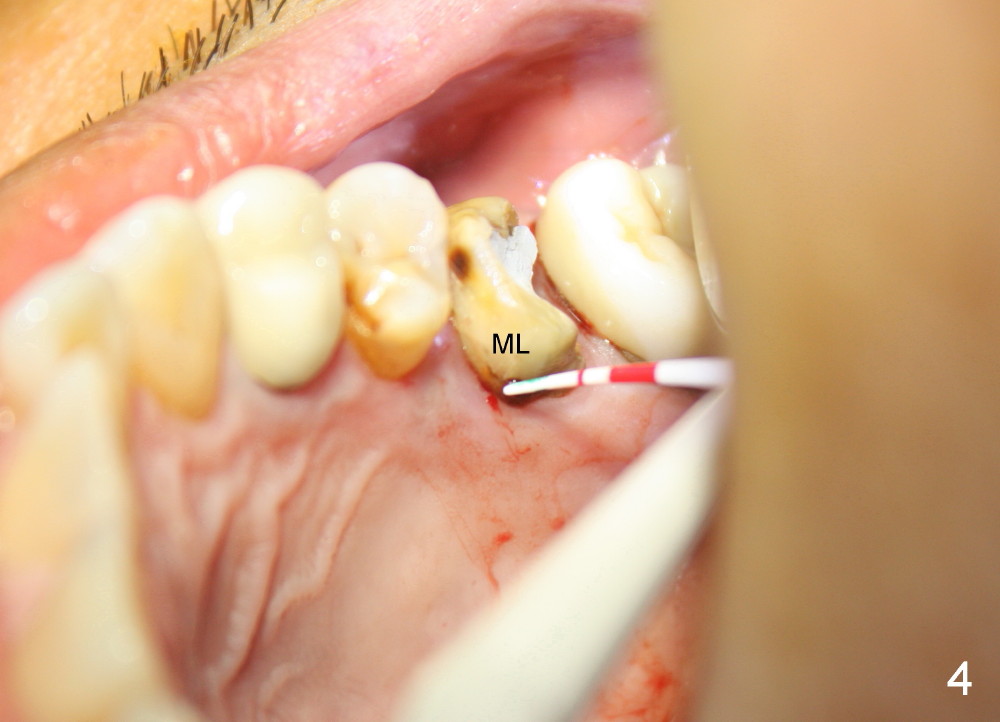

A 49-year-old man has multiple restoration (Fig.1). The tooth #14 appears to be non salvageable (Fig.2-6). The most interesting observation is that the sinus floor (Fig.1 ^) appears to be coronal to the tips of all three roots (mesiobuccal (MB), distobuccal (DB) and palatal (P)). This anatomic feature is confirmed by CBCT study (Fig.2). It will increase insertion torque of an implant to be placed if the sinus floor is raised among the root tips. That is, the apical portion of a large implant is engaged to the area among the apical portion of the three sockets. Let us use Fig.2 Coronal section for design of immediate implant with sinus lift. Click each figure for narrative.